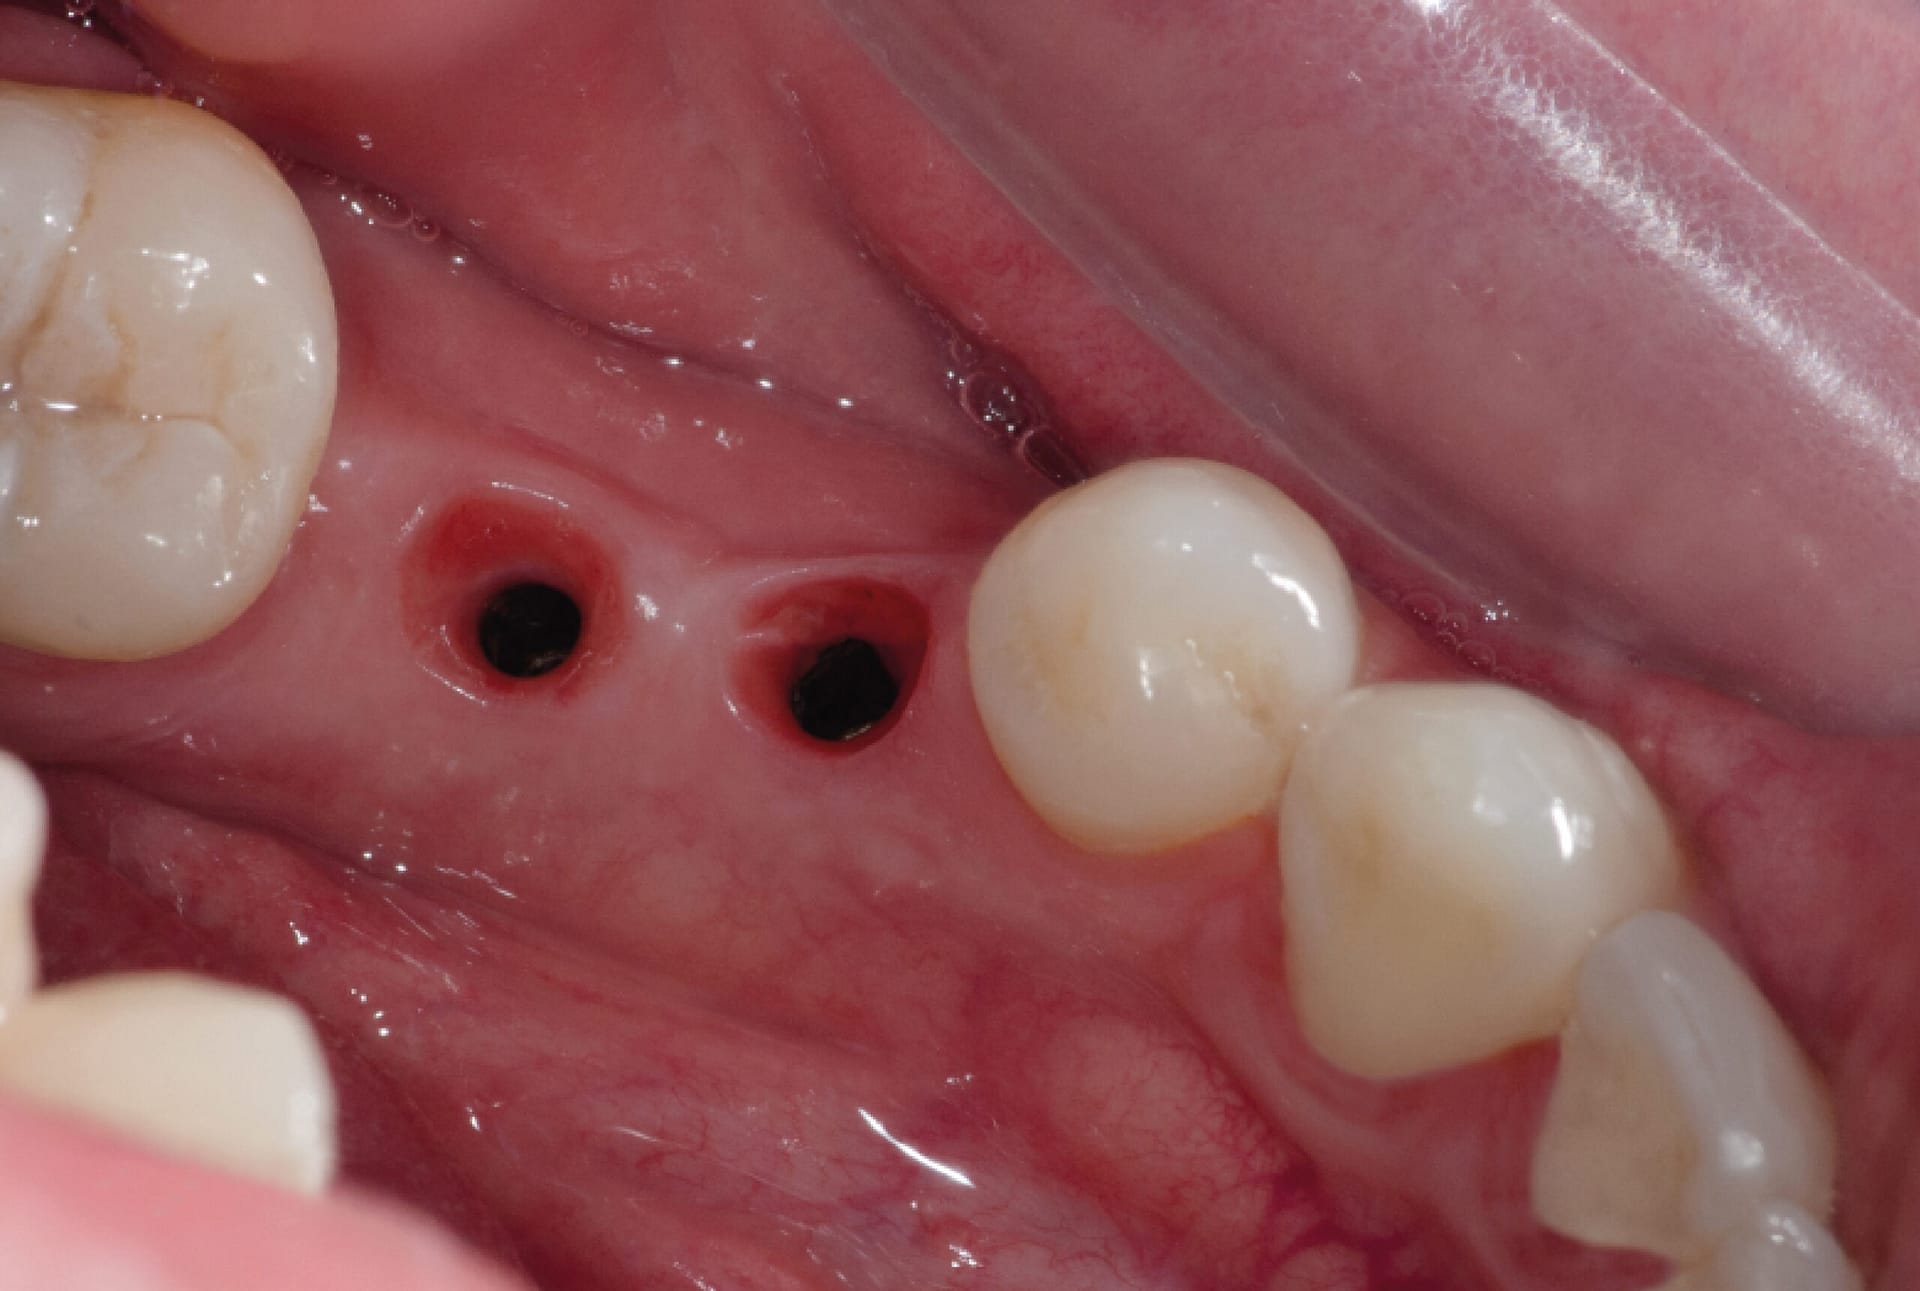

Implantes Dentales

Recupera la estética y función de tu sonrisa en una sola cita.

Implantes Dentales